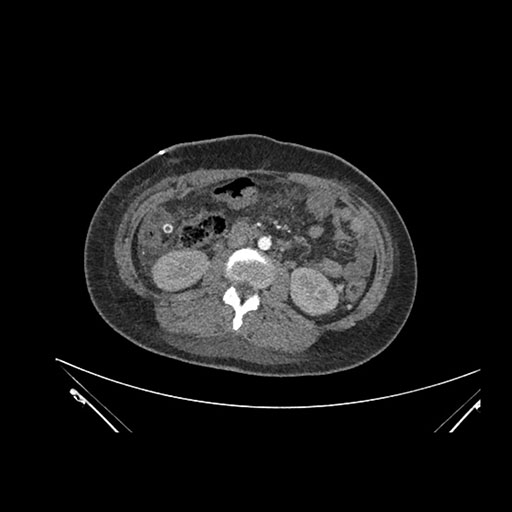

Imaging Analysis

Look through the patient's CT scan to identify any areas of concern for the necessary procedure.

Axial Venous

Based on initial findings, which issue(s) would you be most concerned about?